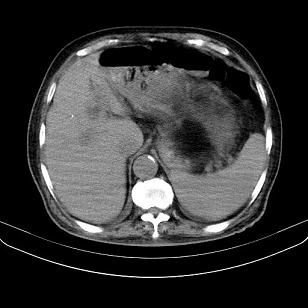

标题: CT21671:男,88岁,左上腹包块 [打印本页]

标题: CT21671:男,88岁,左上腹包块

患者因咳嗽而住院,自觉右上腹包块,无其他不适。

好像一囊腺瘤【太黑,看不清结构】

脂肪肉瘤,应测ct值。